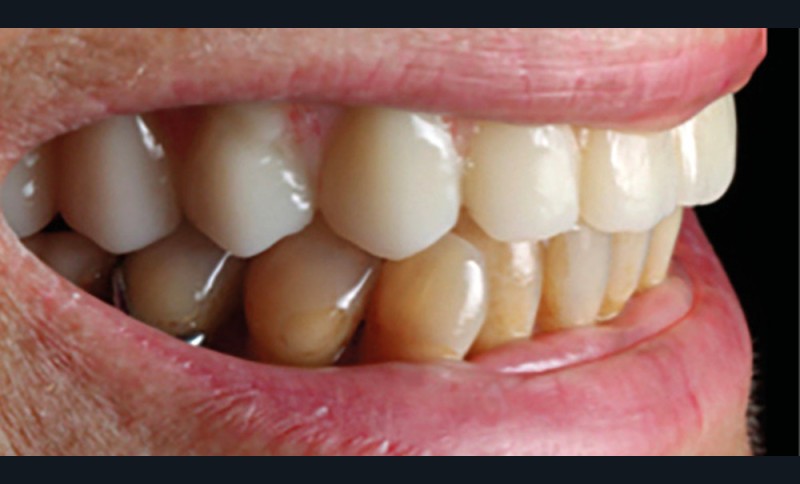

Une patiente de 62 ans, non fumeuse Asa1, porteuse d’une prothèse amovible partielle (PAP) mandibulaire et maxillaire, souhaite bénéficier d’une solution fixée. Il persiste au maxillaire 13, 23, 14 et 24, associées à une forte résorption type FP3 [1, 2] (fig. 1).